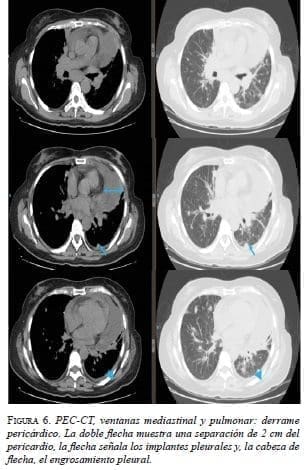

Después de la quimioterapia, en la tomografía por emisión de positrones (PET-CT) se observaron los implantes pleurales, con engrosamiento pleural y pericárdico, y derrame pericárdico. Hubo progresión según los criterios de reacción por PET-CT (Positron Emission Tomography Response Criteria, PERCIST). No se observaron signos de taponamiento cardiaco (figura 6).

Se practicó una ventana pericárdica subxifoidea con instalación de un catéter subcutáneo (tunnelized) pericárdico (figura 7).

El estudio citológico del líquido pericárdico y del bloque celular mostró características serohemáticas; fue positivo para neoplasia maligna: carcinoma (figura 8). La histopatología del tejido obtenido de la ventana pericárdica fue negativa para neoplasia maligna.